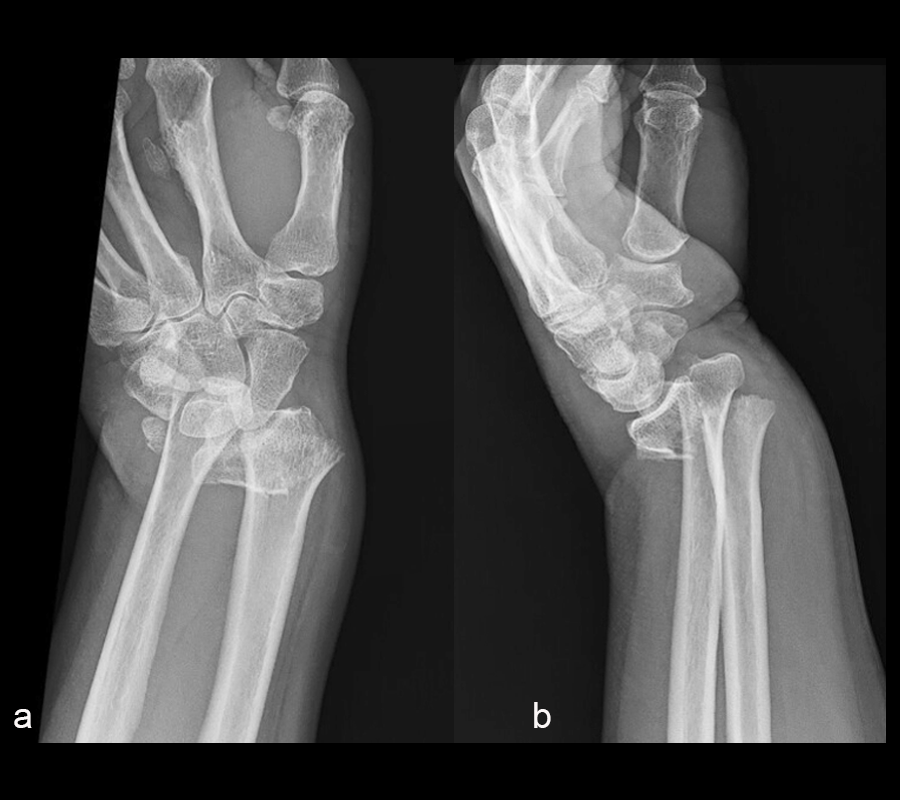

A 60-year-old woman fell on ice from standing height and sustained an injury to the right wrist. Upon admission to the hospital, x-rays revealed a comminuted, intra-articular distal radius fracture with significant dorsal translation and angulation (Fig 1). The patient’s previous medical history included:

The distal radius fracture was treated with open reduction and internal fixation through a volar Henry Approach, using a VOLT™ Two-Column Distal Radius plate. At the 6-week follow-up, x-rays demonstrated a healed fracture (Fig 2). The patient’s pain had resolved and she was regaining range of motion with occupational therapy.